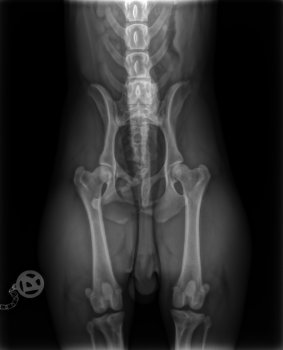

Weitere Röntgentechnik in "Frosch"-Lage

Eine gesunde Hüfte besteht aus runden Femurköpfen, die fest in den Hüftpfannen sitzen, der Oberschenkelknochen ist gerade und nicht zu kräftig.